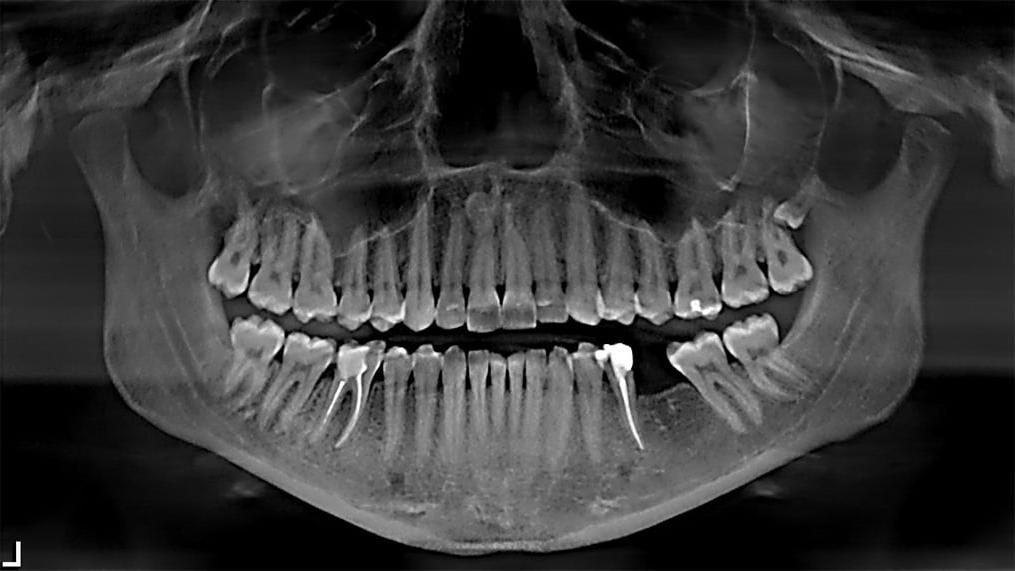

Ортопантомограмма (ОПТГ) — это рентгеновское исследование в стоматологии, предназначенное для получения панорамного снимка зубов и челюстей. Она помогает врачам увидеть скрытые проблемы, такие как воспаление корней зубов, периодонтит, кисты и аномалии развития челюстей.

ОПТГ важна для диагностики и планирования лечения различных заболеваний полости рта, благодаря возможности визуализации общего состояния зубочелюстной системы.

ОПТГ обеспечивает широкий обзор зубочелюстной системы с минимальным уровнем облучения, что делает процедуру безопасной и широко применимой в стоматологической практике.